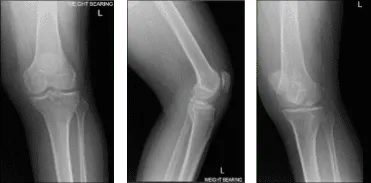

El paciente presentado hoy es un hombre, de 36 años. Se queja de que le duele muchísimo la rodilla izquierda. También presentó el resultado de su radiografía. Existen cambios degenerativos osteoartríticos leves, pero no se han encontrado fracturas agudas. Había probado una gestión conservadora, pero sin ningún beneficio.

Resonancia magnética de rodilla izquierda

Acordamos hacer una resonancia magnética de 3 Tesla de la rodilla izquierda para finalizar el diagnóstico. También hablamos de opciones de tratamiento, incluyendo fisioterapia, inyecciones y también cirugía. El paciente seguirá haciendo terapia de hielo/calor porque le ayuda un poco con la condición de rodilla.

Tras una semana, los resultados de la resonancia magnética recibidos y comentados con el paciente mostraron que, además del derrame articular, se observan algunos cambios degenerativos en el compartimento patelofemoral y en la parte posterior de la meseta tibial medial, que podrían estar relacionados con el SNP focal.